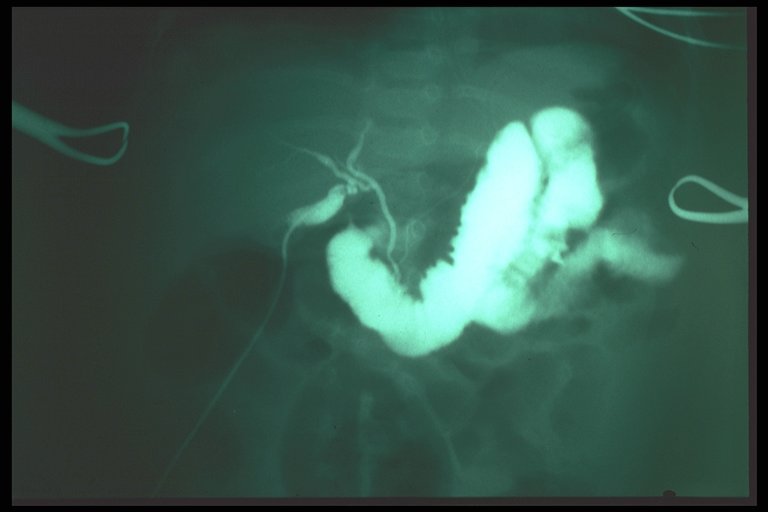

Normal operative cholangiography showed normal tract of common bile duct and both right and left hepatic duct